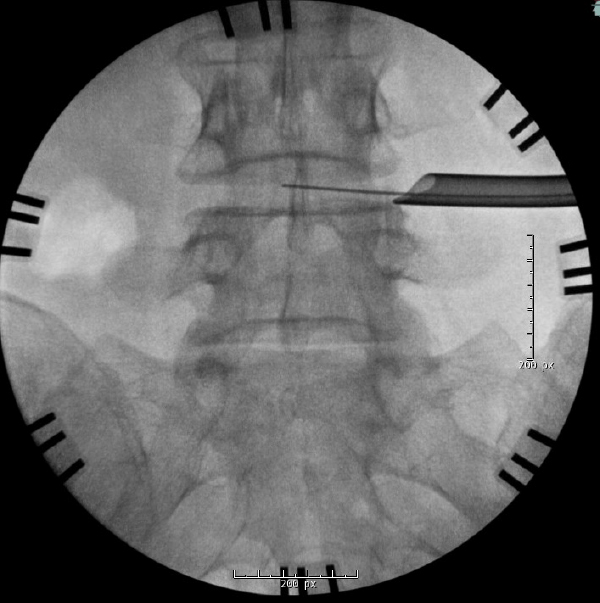

Intraoperative AP fluoroscopy demonstrating removal of the disc fragment with pituitary rongeurs